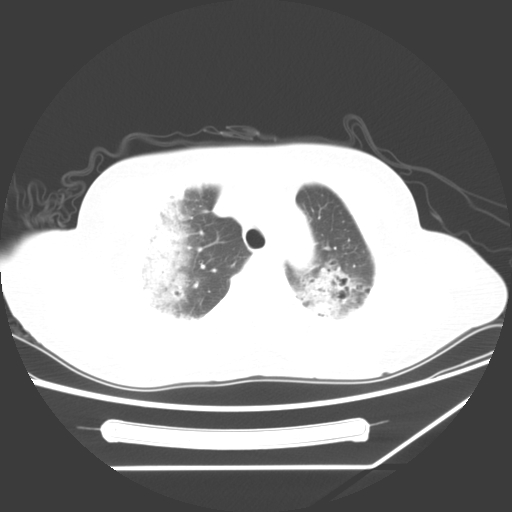

标题: CT25393:病人45岁,咳嗽,吐黄痰带血丝,发热,胸闷月余 [打印本页]

标题: CT25393:病人45岁,咳嗽,吐黄痰带血丝,发热,胸闷月余

1、左肺中央型肺癌并双肺弥漫性转移   2、双肺部感染    3、肺大泡     4、左侧胸腔积液

双侧肺弥漫性病变,可见“空泡征”及“蜂窝征”,考虑肺泡癌可能性大,左侧胸腔积液,考虑胸膜受累可能!

考虑肺泡癌,建议排除感染。

考虑肺泡癌

1)不排除肺泡癌可能。2)左侧胸腔积液。